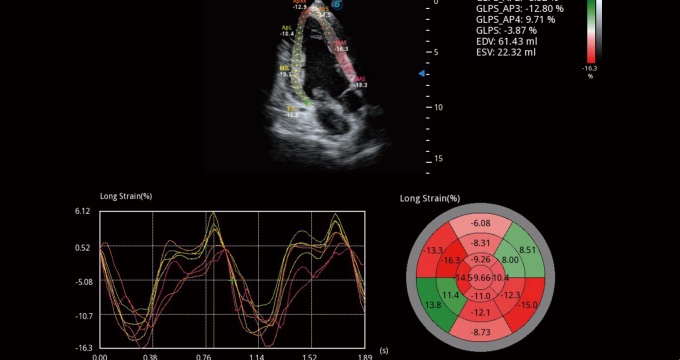

支持运动和药物负荷协议、多心动周期存储选择,为临床观察心肌负荷状态下的室壁节段运动、评估心肌缺血状态提供更多的解决方案。

通过心肌识别技术和二维斑点追踪技术相结合,计算心肌各节段的应变应变率、速度、位移并以曲线图显示,实现整体或者局部心肌定量分析。同时可呈现牛眼图直观和准确诊断心肌的运动情况。